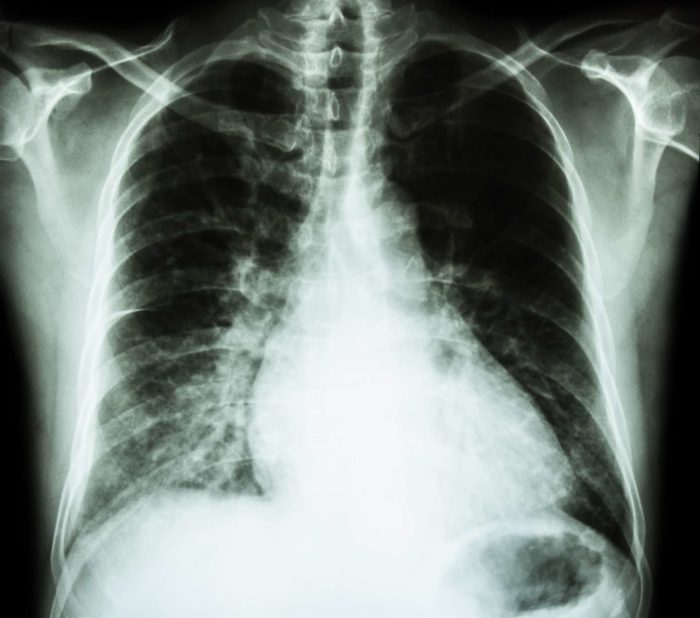

Heart failure is a condition in which the cardiac muscle becomes unable to pump blood and oxygen through the body, which can be caused by high blood pressure or coronary artery disease.  During heart failure, the main chambers of the organ may become stiff and be unable to beat properly.

In more serious cases of heart failure, the heart muscles may become damaged or deteriorated, with the ventricles possibly dilating to the point where the heart can no longer pump blood. Onglyza patients should be wary of any signs of heart failure, including: